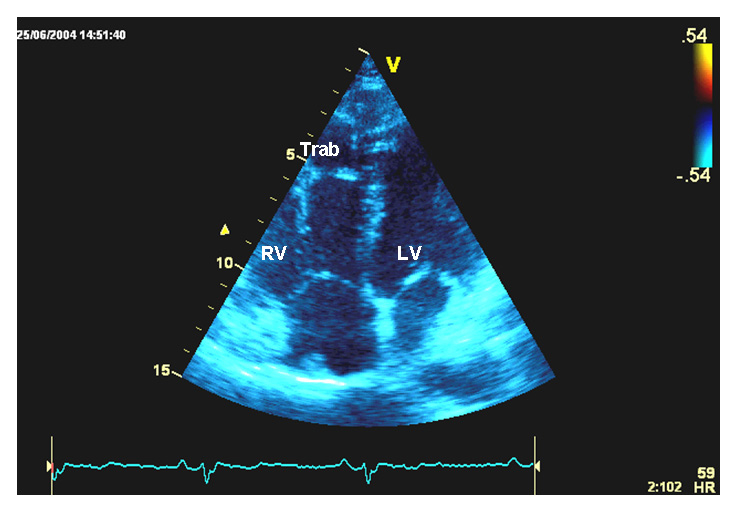

Figure 2

Transthoracic echocardiography, and genetic screening of case 2.

B Apical four chamber view. Right ventricular trabeculations are visible at the free wall level.

RV = right ventricle; Trab = trabeculations; LV = left ventricle.